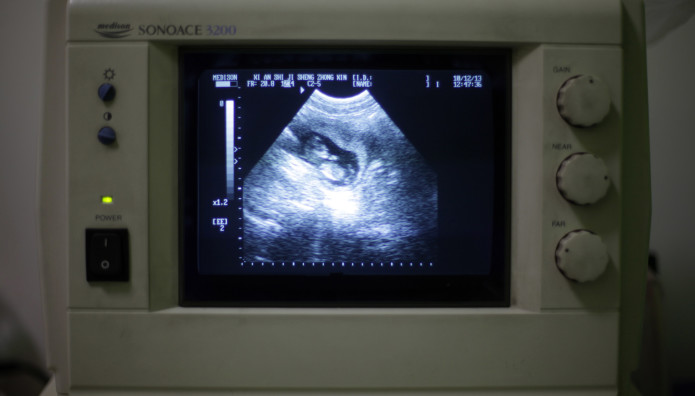

Μια γυναίκα με τη σπάνια πάθηση των δύο μητρών γέννησε δίδυμα, ένα από κάθε μήτρα, τον περασμένο μήνα σε νοσοκομείο της βορειοδυτικής Κίνας, σύμφωνα με αξιωματούχους του τομέα της υγείας και τα κρατικά μέσα ενημέρωσης.